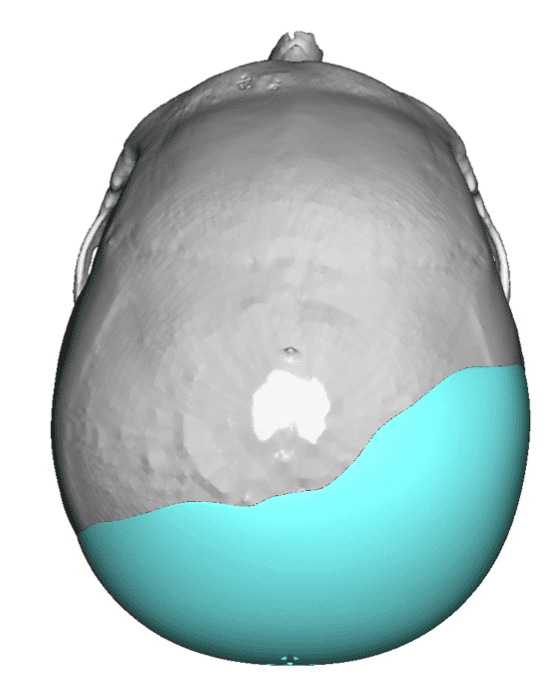

Desire to build up the flatter upper part of the back of his head.

Upper occipital skull augmentation using a custom skull implant.

Desire to build up the flatter upper part of the back of his head.

Upper occipital skull augmentation using a custom skull implant.